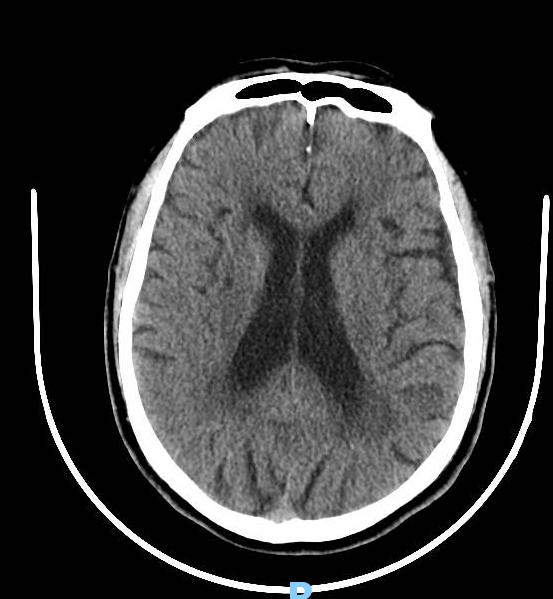

头部CT平扫

70多岁老人因“皮肤瘙痒皮疹4天伴发热2天”入急诊内科住院,经过头部CTA检查发现基底动脉末端动脉瘤,如下图